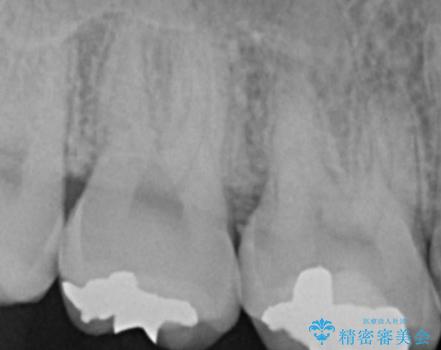

1. 縁下歯石のクリーニングの治療前